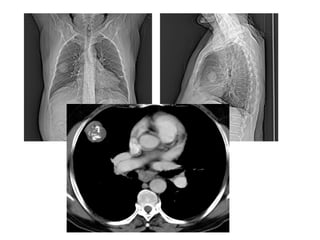

Giải phẩu CT ngực – các mạch máu

lớn.

SVC: tĩnh mạch chủ trên.

Aortic arch: cung đm chủ

Pulmonary artery: đm phổi

Main sterm bronchus: phế quản gốc

63